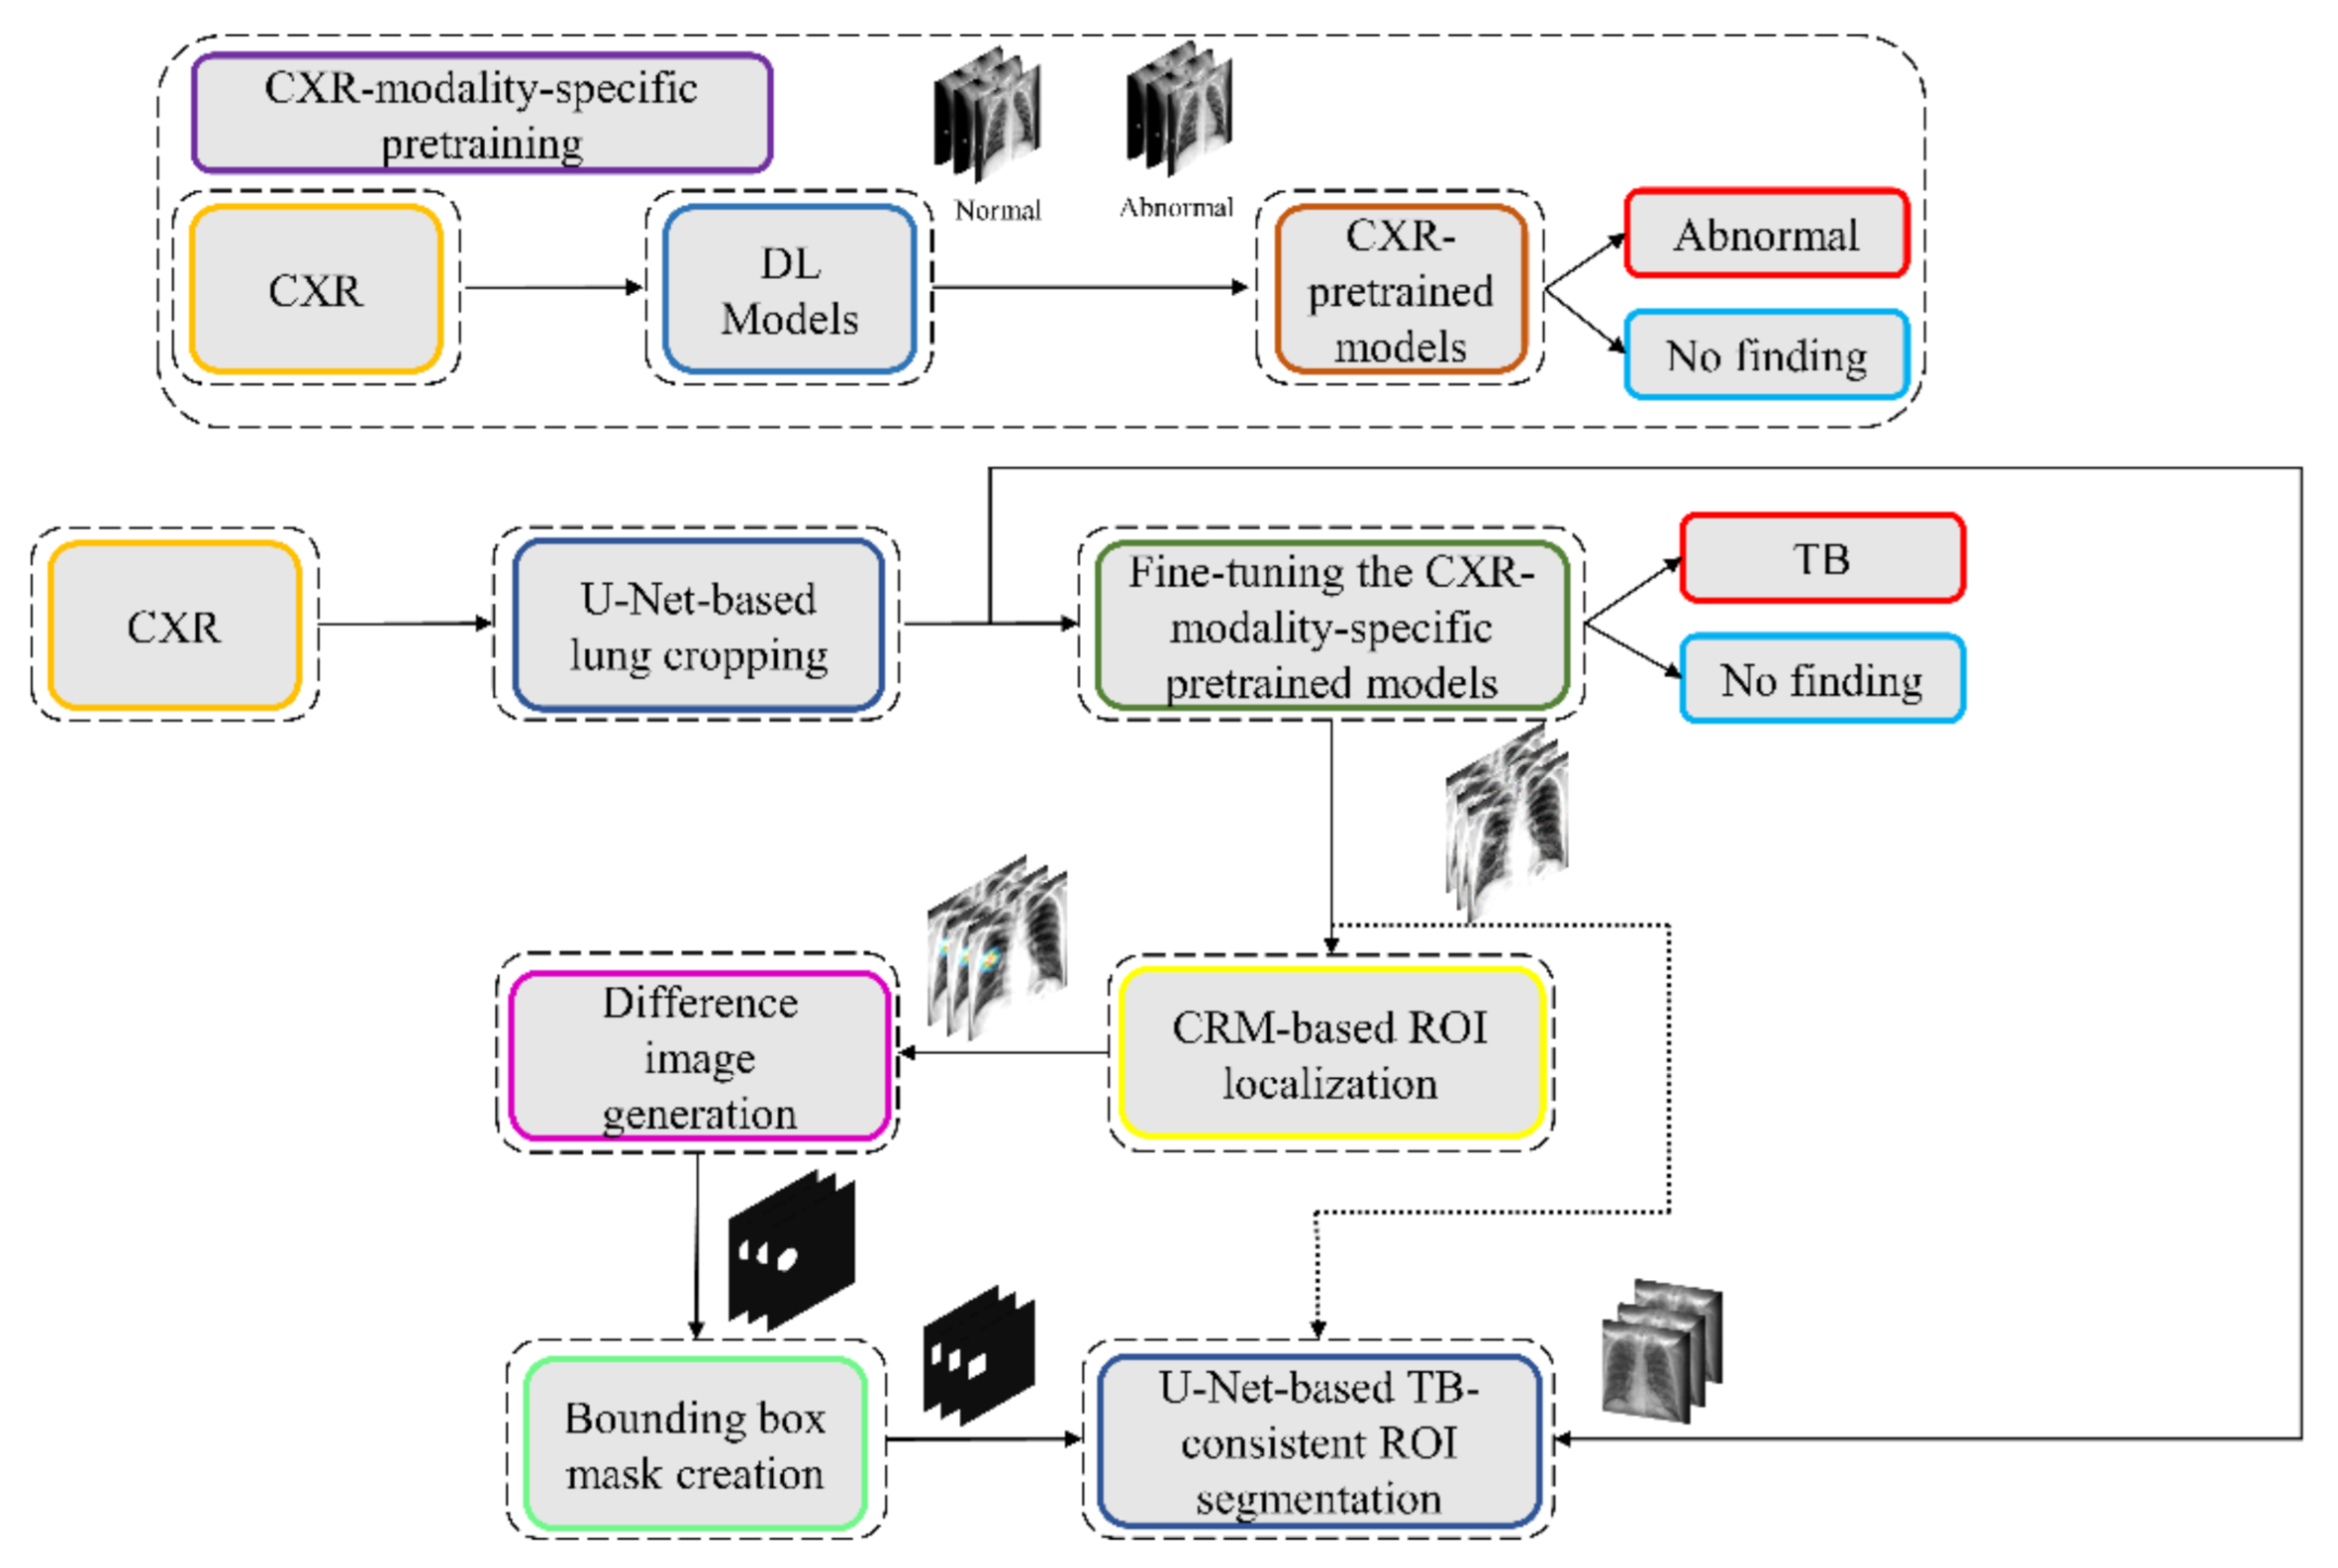

We propose a stage-wise methodology in this retrospective study.

We believe that this is the first study to i) use CXR modality-specific U-Net models to segment TB-consistent manifestations and ii) evaluate non-augmented training and AT segmentation performance using test data derived from the same training data distribution and other cross-institutional collections to determine model robustness and generalization to real-time applications. The combined use of CXR modality-specific U-Net models and AT is expected to improve segmentation performance and could be applied to an extensive range of medical segmentation tasks, including datasets from multiple institutions.

2.3. CXR Modality-Specific Pretraining

17]. CXR modality-specific pretraining converts the weight layers specific to the CXR modality and learns relevant features. The learned knowledge is transferred and fine-tuned to improve performance in a related target task. During this pretraining stage, the models are trained to classify CXRs as showing normal lungs or other abnormal manifestations.

2.5. Model Fine-Tuning and Weak TB-Consistent Localization

The process workflow toward CXR modality-specific pretraining and fine-tuning is illustrated in

Figure 5.

The CXR modality-specific pretrained models are truncated at their deepest convolutional layer and appended with the following task-specific layers: (i) GAP, (ii) dropout (empirically determined ratio = 0.5), and (iii) dense layer with two neurons. The resulting models are fine-tuned using the lung-segmented, combined TB CXR collection, including India TB CXR, Belarus TB CXR, and Shenzhen TB CXR-Subset-1 datasets to classify them as showing normal lungs or pulmonary TB manifestations. The best-performing model from

Section 2.4 is used to segment the lungs in this collection.